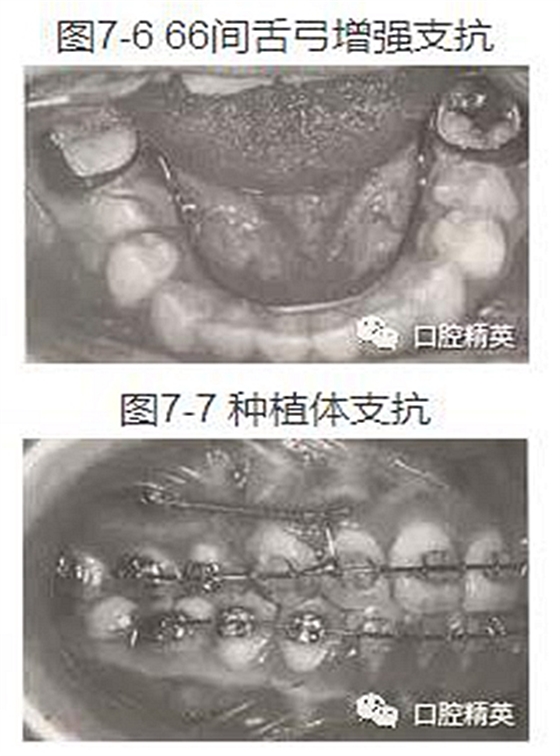

(7)66間加舌弓(圖7-6)。

(8)隨著口腔種植學(xué)的發(fā)展,頜骨內(nèi)種植體己成為口腔正畸治療中的一種支抗手段。種植體支抗的最大特點(diǎn)是可避免以牙齒或牙弓作為支抗結(jié)構(gòu)時(shí)可能出現(xiàn)的移位,保證了矯治過程中對牙列間隙的完全利用(圖7-7)(詳見第十一章)。